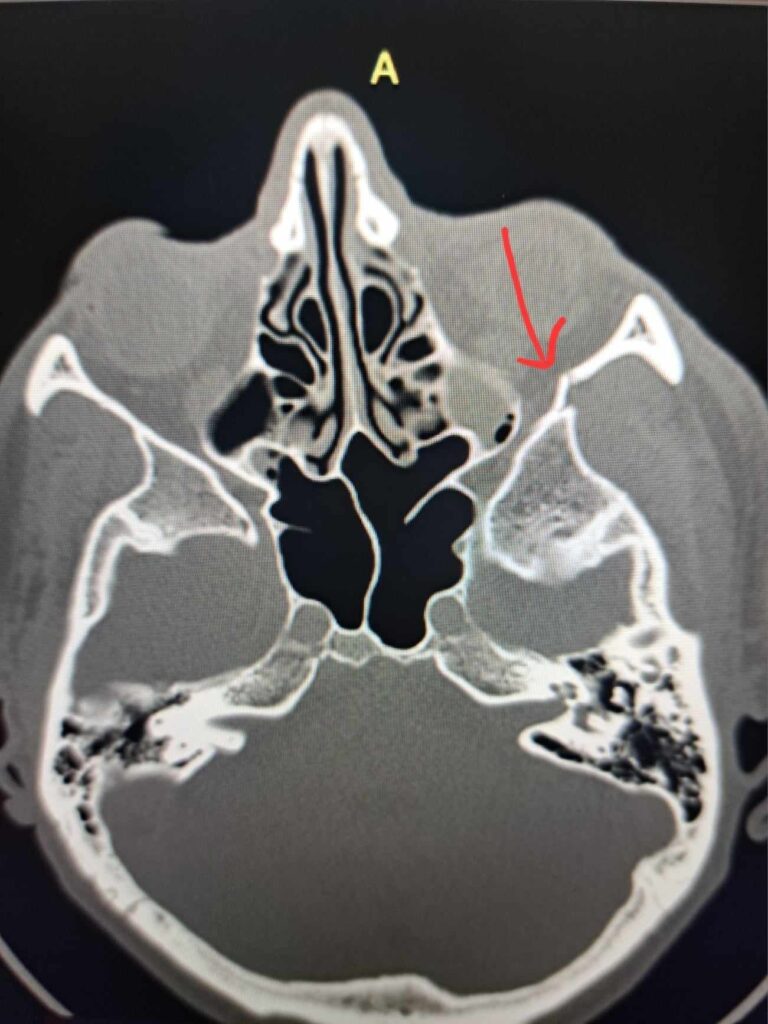

Pieniek. Przy lądowaniu z hopki na trasach w Bielszowicach. Ponad 15 lat jeżdżenia w górach i swoją najpoważniejszą glebę zaliczam w Rudzie Śląskiej. Połączenie pecha na najeździe na hopkę z niekompetencją zarządcy (bądźmy poważni, kto zostawia pieńki bezpośrednio przy lądowaniu) i zamiast witać się z formą życia poznaję uroki chirurgii szczękowo-twarzowej.

O ile rekonstrukcja poszła całkiem sprawnie, a sam pobyt w szpitalu na Francuskiej będę wspominał wyjątkowo dobrze, o tyle po zaleceniach lekarskich mówiących by nie trenować minimum 6 tygodni od operacji już wiedziałem, że plan z formą na urodziny wziął w łeb. Oczywiście nie zrobiłem 1,5 miesięcznej przerwy od treningów, ale pierwsze bardzo spokojne jeżdżenie na rowerze stacjonarnym wpadło równo tydzień po operacji.